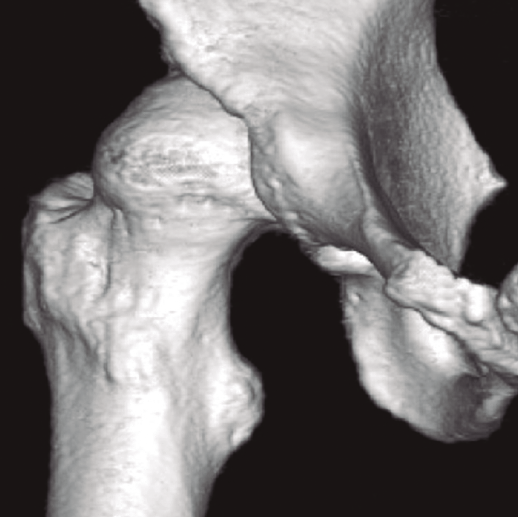

- El grupo de Berna(11)y el de la Mayo Clinic han descrito signos radiológicos cuya sola presencia aumenta la probabilidad de mal resultados en comparación con la ausencia de los mismos: a) osteofito en la fosa (multiplica por 3,2 veces la posibilidad de mal resultado); b) geodas subcondrales > 5 mm (multiplica por 4,1); y c) lesiones condrales de grado 3-4 que afecten al menos a 60° de la circunferencia acetabular (multiplica por 4,6). Además, los pacientes de CFA intervenidos con el hallazgo preoperatorio de estos 3 signos asocian un 0% de supervivencia a 6 años y los que tienen el a) y el c) un 20% a 6 años. De ahí que debamos buscar la presencia de estos y otros signos descritos en el artículo para informar a nuestro paciente de las posibilidades de éxito (Figura 1).

Figura 1. Paciente de 44 años con espacios < 2 mm en la zona 3, geodas subcondrales y osteofito de fosa. Pese a los factores en su contra, sus expectativas razonables nos inclinaron por la cirugía artroscópica. En la imagen de la derecha, resección del osteofito de fosa.

Figura 2. Paciente con geodas subcondrales acetabulares y en cabeza femoral, osteofito de contrachoque posteroinferior, espacios < 2 mm, incorrecta resección de CAM previo y defectos capsulares marcados.